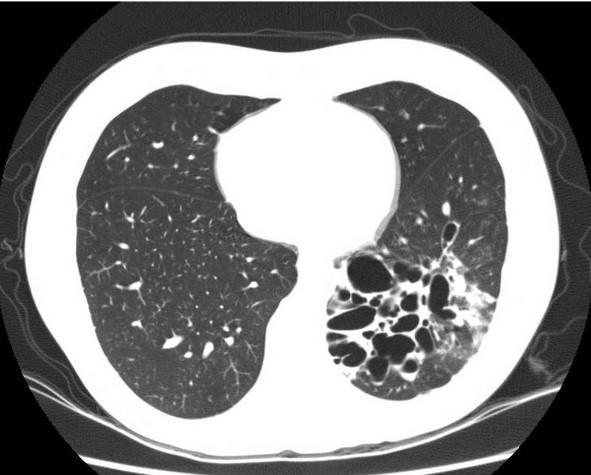

Рисунок 3:КТ ОГП: односторонние бронхоэктазы в легких